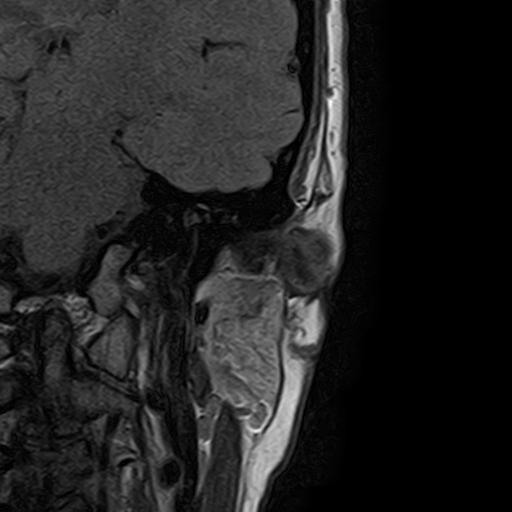

Височно-нижнечелюстной сустав является парным комбинированным суставом и имеет сложное строение. В него входят суставные ямки височной кости, суставные головки нижней челюсти и расположенные между ними хрящевые пластинки – мениски, выполняющие роль амортизаторов.

Сустав имеет мощный связочный аппарат, который позволяет ему выдерживать большую нагрузку при пережевывании пищи. Сложное строение и значительные нагрузки способствуют развитию в суставе дегенеративно-дистрофических и воспалительных заболеваний.

Чаще всего дисфункция височно-нижнечелюстного сустава обусловлена внутренним повреждением, смещением мениска и суставной головки нижней челюсти. Для определения степени смещения внутрисуставных структур выполняется функциональная проба с проведением МРТ в двух положениях:

• с закрытым ртом;

• с открытым ртом.

Магнитно-резонансная томография является наиболее точным и эффективным методом диагностики поражения височно-нижнечелюстных суставов, так как позволяет получить детальную информацию о состоянии не только костей, но и связочного аппарата, хрящей, менисков, жевательных мышц, окружающих мягких тканей.

При проведении магнитно-резонансной томографии на изображениях визуализируются: височная кость, головка мыщелкового отростка нижней челюсти, суставная щель. Помимо костных структур МРТ позволяет оценить состояние мягких тканей – внутрисуставного диска и связочного аппарата височно-нижнечелюстного сустава, жевательных мышц.

МРТ ВНЧС с капой включает в себя два протокола: с открытым ртом и с закрытым ртом. Данная функциональная проба позволяет проследить степень смещения внутрисуставных анатомических структур и оценить биомеханику движений в суставе.